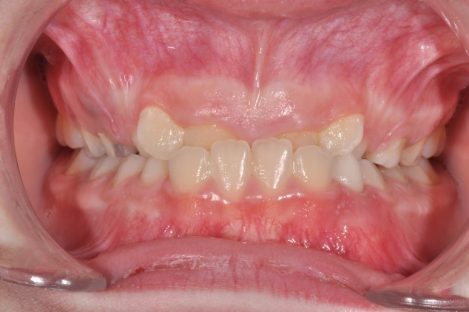

Ортодонтско лечение при множествена хиподонтия. Клиничен случай.

Статията обсъжда клиничните аспекти на проблема – множествена хиподонтия. Решението и планът на лечение при тези пациенти включват дългосрочни цели и съобразяване с костното развитие на пациента както до завършване на растежа му, така и при неговото остаряване. Често лечението на тези клинични случай завършват с протетичното им възстановяване. Затова ортодонтското лечение трябва да е съобразено с крайното дефинитивно възстановяване на съзабието.